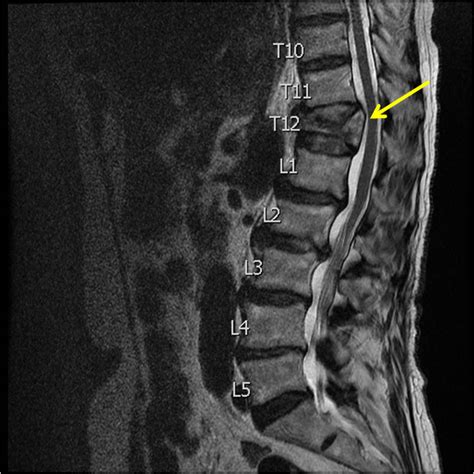

Imaging Tests

Imaging tests are crucial for confirming the diagnosis and determining the severity of the fracture.

• X-rays: These are often the first step in evaluating a suspected compression fracture. They can reveal the presence of a fracture and help assess its stability.

• CT Scans: CT scans provide more detailed images of the spine and can help identify subtle fractures or other abnormalities.

• MRI Scans: MRIs are useful for evaluating soft tissues, such as ligaments and spinal cord. They can help detect nerve compression or other complications.

• Bone Density Tests: Also known as DEXA scans, these tests measure bone density and can help diagnose osteoporosis, a common cause of compression fractures.